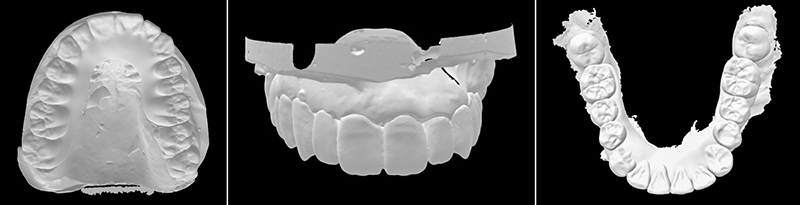

Le traitement débute par la numérisation des arcades dentaires et de l’occlusion statique. En fin de séance, ces empreintes optiques seront transférées au laboratoire de prothèse pour la confection d’une prothèse amovible partielle transitoire mandibulaire et d’un bridge provisoire maxillaire.

Un enregistrement des références et des plans pertinents (le plan bi-pupillaire, la position du bord incisif, les lignes médianes faciales et dentaires) est effectué sur les photographies et modèles numériques afin d’intégrer des informations précises dans le flux de travail numérique pour le prothésiste. Leur combinaison au sein du logiciel de laboratoire permet la réalisation d’un wax-up numérique de 17 à 26.

La conception numérique du sourire sert de guide de positionnement afin de respecter les proportions verticales (positionnement du bord libre des incisives) et horizontales des dents maxillaires. Après suppression virtuelle des dents à extraire, la conception de la prothèse amovible partielle transitoire est réalisée pour la mandibule.

Fig. 05 : simulation numérique maxillaire et mandibulaire.